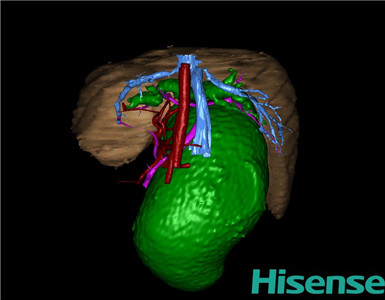

术前三维重建及手术方案设计:

将0.625mm双源薄层CT资料的静脉期和动脉期Dicom格式文件导入海信CAS系统。

通过调节窗宽窗位调整CT序号,对肝实质,胆囊,胆总管,下腔静脉,肝动脉、门静脉及肝静脉等进行三维重建;系统自动计算肝脏体积。

术前手术方案的规划。

术前三维重建:

重建图片